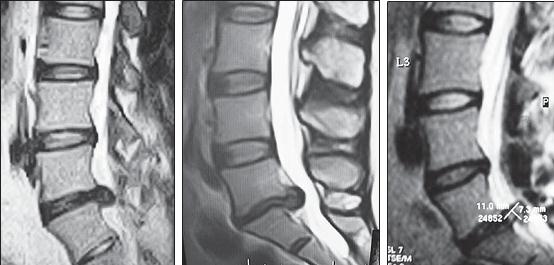

На серии МРТ № 26 наблюдаются секвестрированные грыжи межпозвонковых дисков в поясничном отделе позвоночника в сегментах LIV—LV LV—SI с каудальной (каудальной — расположенной ближе к нижней части туловища, направленной вниз) миграцией секвестра (фрагментов межпозвонкового диска) МРТ № 27 ![]() На серии МРТ № 27 наблюдаются секвестрированные грыжи межпозвонковых дисков в поясничном отделе позвоночника в сегментах L]-Sl с краниальной (вверх) миграцией секвестра (фрагментов межпозвонкового диска) Должен заметить, что по моим наблюдениям, к сожалению, практически все существующие на сегодняшний день методы лечения дегенеративно-дистрофического процесса, в том числе и осложнённого грыжами межпозвонковых дисков, направлены на устранение болевого синдрома. Проще говоря, лечат следствие, а не причину! Обращаю ваше внимание на следующий факт. Бывают грыжи межпозвонковых дисков, которые не вызывают никакой симптоматики, так называемые «немые» грыжи. Как правило, они имеют срединную локализацию. Некоторые «специалисты», практикующие в области вертебрологии, ошибочно считают, что такие грыжи абсолютно безопасны и лечить их нет необходимости. При этом навязывают своё (в данном случае необоснованное, ошибочное) мнение, что межпозвонковые грыжи опасны лишь тогда, когда вызывают боли. К сожалению, это далеко не так! МРТ № 28